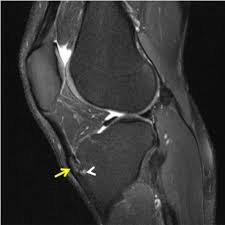

Knee disease osgood schlatters in adults. In four cases a true joint had formed between an ossicle in the patellar ligament and a facet on the tibia. Osgood-Schlatter disease is a painful condition causing inflammation just below the knee. The tendon below your kneecap called the patellar tendon attaches to the tibial tuberosity on the shinbone called the tibia.

Osgood-Schlatter disease most often occurs during growth spurts when bones muscles tendons and other structures are changing rapidly. The pain may come and go. There may also be inflammation of the patellar tendon which stretches over the kneecap.

Friday April 05 2019. Pain that gets worse with exercise or activity. Seven adults with the sequelae of Osgood-Schlatters disease presented after experiencing symptoms for an average of eight years. Osgood Schlatter disease symptoms. Osgood-Schlatter exercises are used to strengthen the muscles around the knee joint principally the quadriceps hamstrings and gastrocnemius muscles. Common in adolescents during growth spurts Osgood-Schlatter disease can affect adults if not properly assessed and treated. Pain and tenderness in front of the knee. This bony protrusion is called the tibial tuberosity. Adults with continued symptoms may need surgical treatment if they fail to respond to conservative measures.

Osgood-Schlatter is a common condition in young athletes and growing adolescents that refers to inflammation of a growth plate at the knee. Osgood Schlatter Disease Surgery In extreme cases surgery may be used to get rid of Osgood-Schlatter disease. Osgood-Schlatter is a common disease with most cases resolving spontaneously with skeletal maturity. The purpose of this study is to describe. The pain may come and go. There may also be inflammation of the patellar tendon which stretches over the kneecap. Osgood-Schlatter is a common condition in young athletes and growing adolescents that refers to inflammation of a growth plate at the knee.